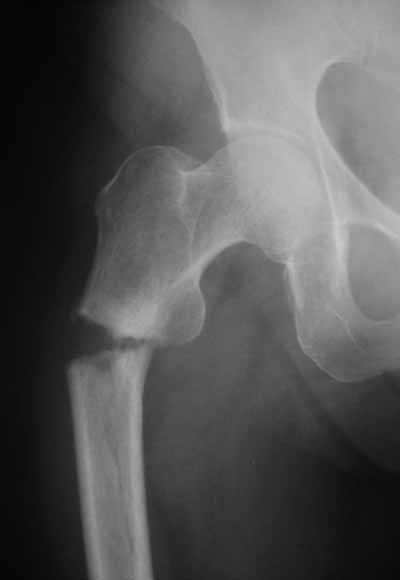

> Здравствуйте коллеги ! Прооперировали женщину 72 лет с Диагнозом: Чрезвертельный перелом

> левого бедра. Первый раз поставили PFN A (SYNTHES) см R-gr.

Да? Качество рентгенограмм конечно неочень, но ведь это нестабильный перелом 31.А2.2, не так ли?